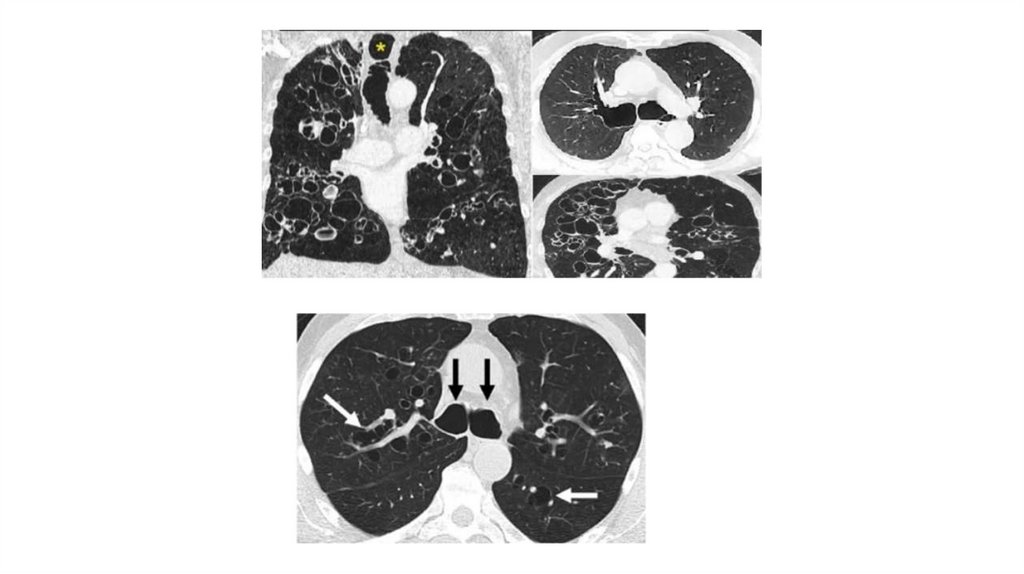

Врожденные и наследственные заболевания легких у детей